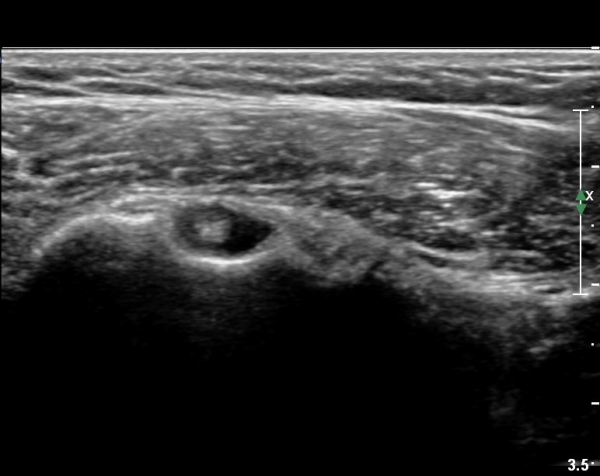

ȸÀü±Ù°³°£°Ý(rotator cuff interval) Ⱦ´Ü¸é°Ë»ç¿¡¼­ ÀÌµÎ¹Ú±Ù°Ç ¿ÜÃø¿¡ ±Ø»ó°ÇÀÌ °üÂûµÇÁö ¾Ê°í

´ë°áÀý Ç¥ÃþÀÇ »À°¡ ¿ïÅüºÒÅüÇÏ°Ô º¯ÇÏ¿´´Ù(±×¸² 1, 2)

ÀÌ´Â ½ÉÇÑ Ãæµ¹ÁõÈıºÀÇ °á°úÀ̰í ȸÀü±Ù°³ ÆÄ¿­À» °­·ÂÈ÷ ¾Ï½ÃÇÏ´Â ¼Ò°ßÀÌ´Ù.